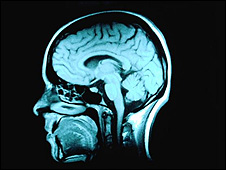

La gente sorda informa que su visión periférica es más aguda. La gente sorda de nacimiento es capaz de reprogramar las áreas de su cerebro asignadas al oído para mejorar su visión, afirma un estudio. Tanto las personas sordas como las invidentes frecuentemente afirman que, para compensar, sus otros sentidos son más agudos. Sin embargo, hasta ahora no se sabía cómo se lograba este proceso cerebral. La mejora en la visión periférica, que a menudo dicen tener las personas con sordera, podría generarse en la zona cerebral que normalmente se encarga del oído periférico. Científicos de la Universidad de Ontario Occidental, Canadá, se abocaron a probar esa teoría y, en el reporte sobre los resultados sobre el que informa la revista Nature Neuroscience, señalan que el cerebro tiende a aprovechar todo su potencial. Compensación Los investigadores utilizaron gatos con sordera congénita para probar qué partes del cerebro se ocupaban de esta compensación. Los animales fueron sometidos a pruebas en las que se destellaban luces en la periferia de su visión normal. Cuando la corteza auditiva -la parte del cerebro que normalmente procesa la información de sonidos- se desactivaba temporalmente, la visión periférica mejorada de los gatos parecía también apagarse. En un estudio más detallado, el equipo descubrió que la parte de la corteza auditiva responsable era la zona normalmente encargada de detectar los sonidos periféricos. Tal como explica el doctor Stephen Lomber, quien dirigió la investigación, "el cerebro es un órgano muy eficiente y no permite que ninguno de sus espacios se desperdicien". "El cerebro desea compensar por el sentido perdido con mejoras en otras áreas que son beneficiosas". "Por ejemplo, si usted es sordo, se beneficiaría al ver en su visión periférica a un auto que se acerca desde lejos. Como no puede oír al auto acercándose al lado, sí puede verlo con más agudeza y detectar qué tan rápido se está moviendo", señala el científico. Y agrega que el entendimiento de lo que ocurre dentro de la corteza auditiva en ausencia de información de sonido puede ayudar a los médicos a comprender lo que ocurre cuando una persona con pérdida de oído se somete a un implante coclear. "Si el cerebro se reprograma a sí mismo para compensar por la sordera, ¿qué ocurre cuando se restaura el oído?", pregunta el doctor Lomber. Tiempo de reacción El cerebro se reprograma para compensar. La doctora Joanna Robinson, investigadora del Real Instituto Nacional para Personas con Sordera (RNID) del Reino Unido, recibe positivamente los resultados del estudio. "Esta investigación -expresa- apoya estudios anteriores que afirman que la gente con sordera congénita tienen un campo visual más grande que la gente que puede escuchar". "Otros estudios que nosotros financiamos recientemente mostraron que los adultos sordos también pueden reaccionar a objetos en su visión periférica con más rapidez que los adultos que sí escuchan, pero los niños sordos reaccionan más lentamente que sus pares que escuchan". "Esto indica que quizás toma algún tiempo para que la parte auditiva del cerebro logre hacer el cambio para compensar y procesar la información visual", explica la experta.